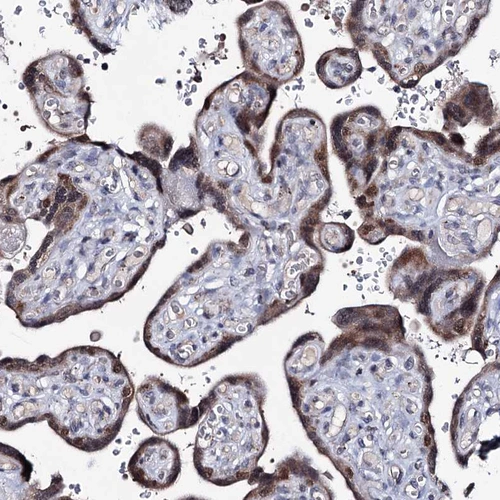

Immunohistochemical staining of human placenta shows strong cytoplasmic and nuclear positivity in trophoblastic cells.